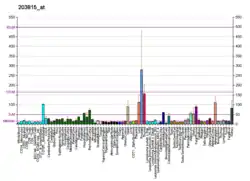

Glutathione S-transferase (GST) theta 1 (GSTT1) is a member of a superfamily of proteins that catalyze the conjugation of reduced glutathione to a variety of electrophilic and hydrophobic compounds. Human GSTs can be divided into five main classes: alpha, mu, pi, theta, and zeta. The theta class includes GSTT1 and GSTT2. The GSTT1 and GSTT2 share 55% amino acid sequence identity and both of them were claimed to have an important role in human carcinogenesis. The GSTT1 gene is located approximately 50kb away from the GSTT2 gene. The GSTT1 and GSTT2 genes have a similar structure, being composed of five exons with identical exon/intron boundaries.[3]